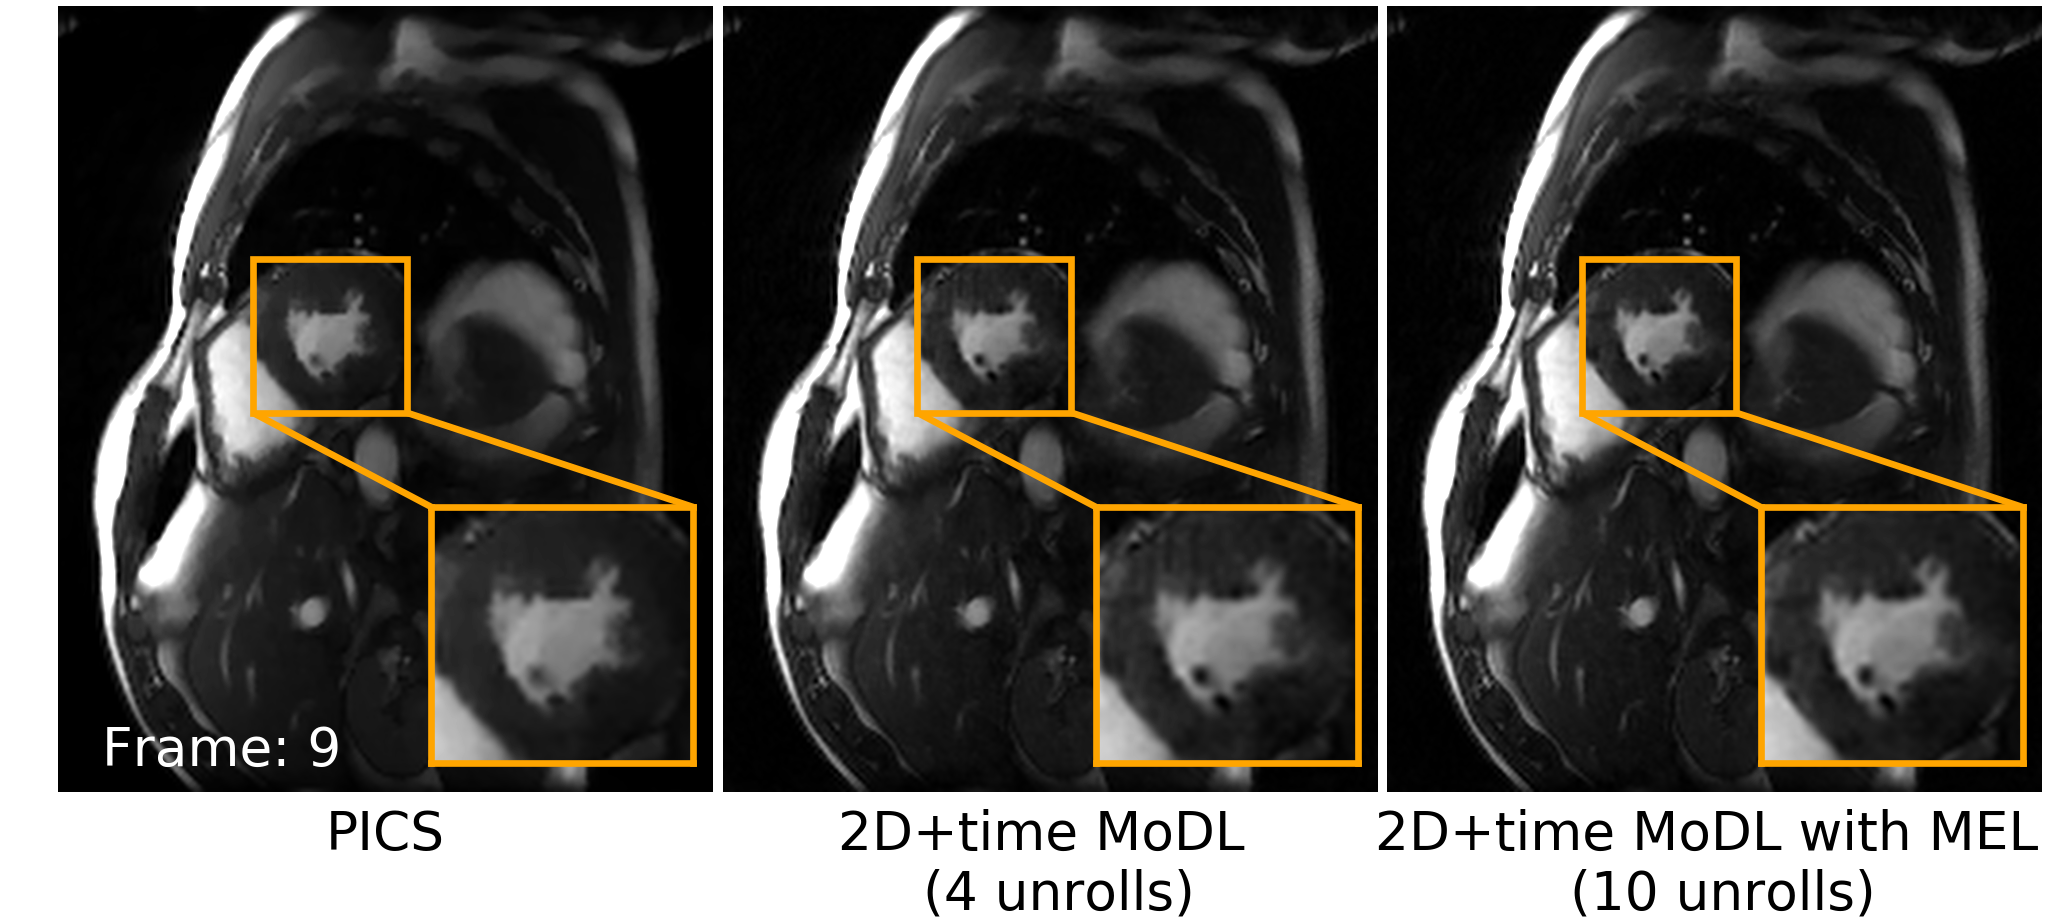

Figure 4 shows a comparison of different methods for 3D reconstruction. Instead of learning from only 2D axial view slices (Figure 1 a), 3D MoDL with MEL captures the image features from all three dimensions. Zoomed-in details indicate that 3D MoDL with MEL is able to provide more faithful contrast with more continuous and realistic textures as well as higher pSNR over other methods. Figure 5 demonstrates that MEL enables the training of 2D+time MoDL with a large number of unrolls (10 unrolls), which outperforms MoDL with 4 unrolls with respect to image quality and y-t motion profile. With MEL, MoDL with 10 unrolls resolves the papillary muscles (yellow arrows) better than MoDL with 4 unrolls. Also, the y-t profile of MoDL with 10 unrolls depicts motion in a more natural way while MoDL with 4 unrolls suffers from blurring. Meanwhile, using 10 unrolls over 4 unrolls yields an improvement of 0.6dB in validation pSNR.

Refer to caption

Figure 5: a) Short-axis view cardiac cine reconstruction of a healthy volunteer on a 1.5T scanner. k-Space data was retrospectively undersampled to simulate 14-fold acceleration with 25% partial echo (shown in b) and reconstructed by: 2D+time MoDL with 4 unrolls, 2D+time MoDL with MEL and 10 unrolls. c) Validation pSNR of MoDL with 4 unrolls and MoDL with 10 unrolls.